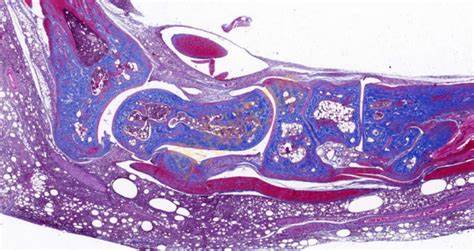

Masson染色是一种用于显示组织中纤维成分的特殊染色方法,主要用于区分胶原纤维和肌纤维,在病理学和组织学研究中有广泛的应用。**一、染色原理**1. 试剂作用 - **酸性复红**:它是一种酸性染料,能够将细胞质、肌纤维等染成红色。在染色过程中,酸性复红与肌纤维中的碱性蛋白结合,使肌纤维呈现出红

18326618418 立即咨询Masson染色是一种用于显示组织中纤维成分的特殊染色方法,主要用于区分胶原纤维和肌纤维,在病理学和组织学研究中有广泛的应用。

**四、结果观察与分析**

1. 细胞核

- 经过Weigert铁苏木精染液染色后,细胞核呈现黑色。可以观察细胞核的大小、形状、位置以及核内结构(如核仁),这有助于判断细胞的类型和状态。

2. 肌纤维

- 被酸性复红染色后呈红色,通过观察肌纤维的分布、走向和形态,可以了解肌肉组织的结构和功能。例如,在心肌组织中,心肌纤维呈分支状,相互连接成网状;在平滑肌组织中,肌纤维呈长梭形,排列较为规则。

3. 胶原纤维

- 被苯胺蓝染色后呈蓝色。可以观察胶原纤维在组织中的分布和含量,这对于研究组织的纤维化程度、创伤修复等过程具有重要意义。例如,在肝脏纤维化的组织中,会出现大量蓝色的胶原纤维增生。